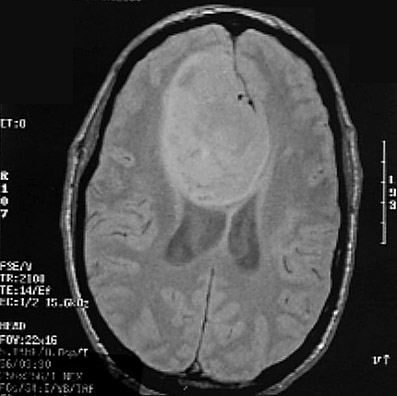

Click on the glioma in the MRI scan below:

This is a sagittal MRI scan demonstrating a large glioma impinging upon the ventricular system. A transverse view is shown below